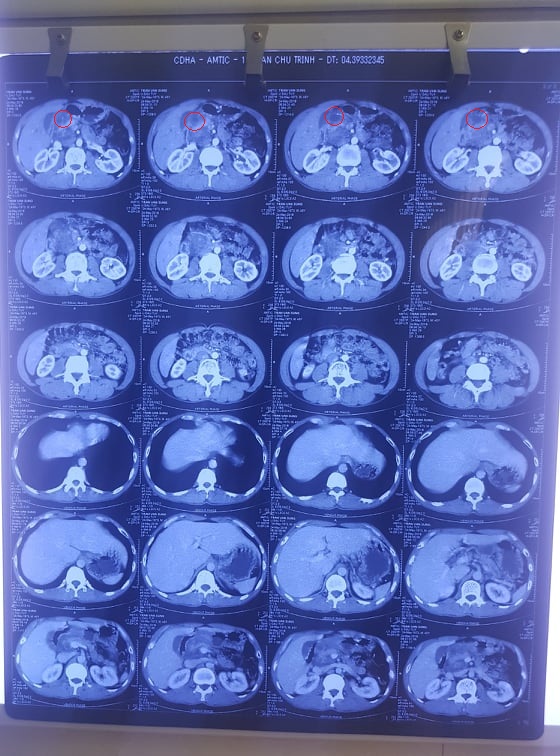

• Chụp CT: Khối dạng nang vùng đầu tụy KT 1,8 cm (Trước điều trị 4,5 x 4,3cm).

Kết quả sau khi uống Kilcel 500mg một tháng